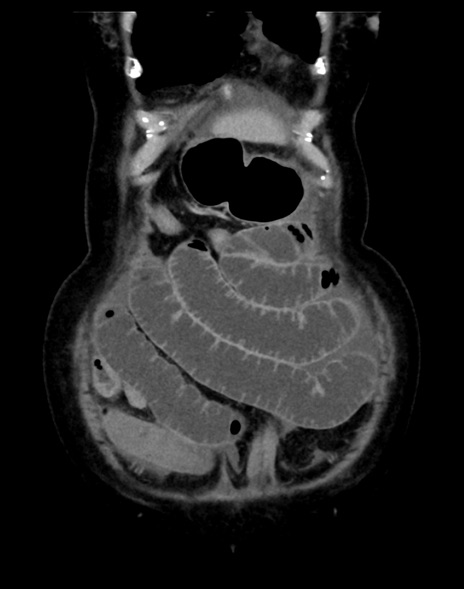

(横断像)1日半後